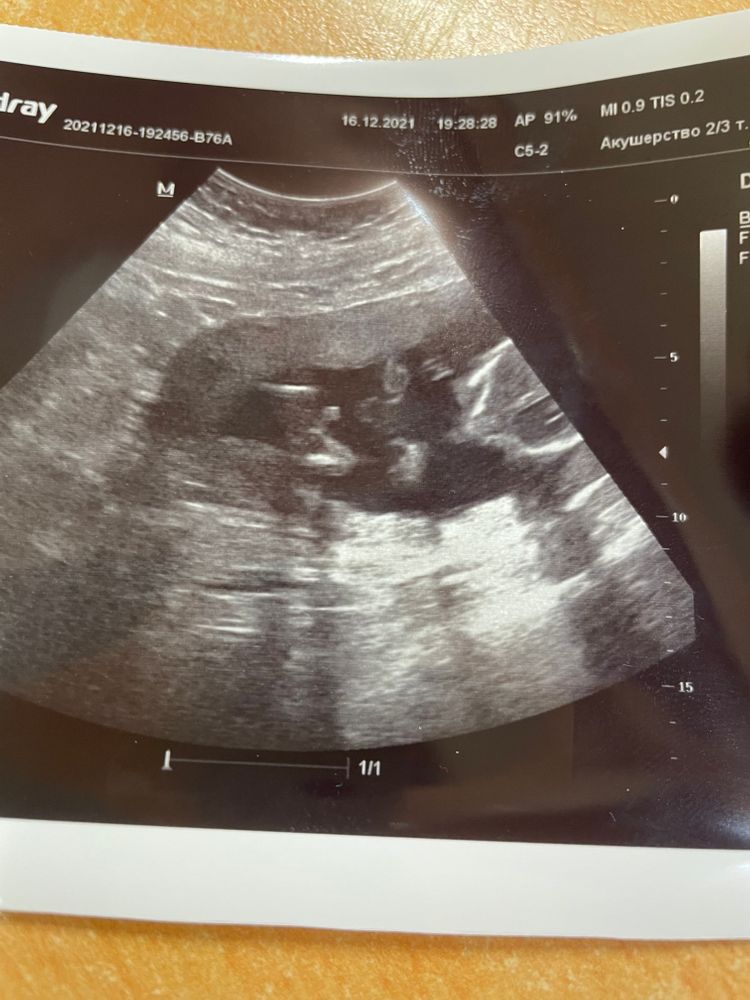

О Боже, я не верю😳у нас будет сын… СЫН!!! 💙 муж прыгает от счастья, я пока ещё не могу поверить. Мне самое главное что здоров и полностью соответствует сроку и чуть опережает👍 после 2 девочек, третий мальчик 👦 это совсем другое ощущение 🤞Но я очень рада, и благодарю Бога, что все так как есть 🙏 и вот собственно наше достоинство )) мальчик же????👦